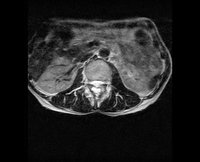

骨结核大多是由肺结核继发的。属于结核菌的隐匿性感染。结核菌核大多首先发生在肺部,在肺部感染后通过血液的传播可以到全身很多系统去,骨结核不是单纯的病变,是全身疾病在局部的表现。下面我们来学习一下有关骨结核病的知识。>>>不想看文章,直接咨询